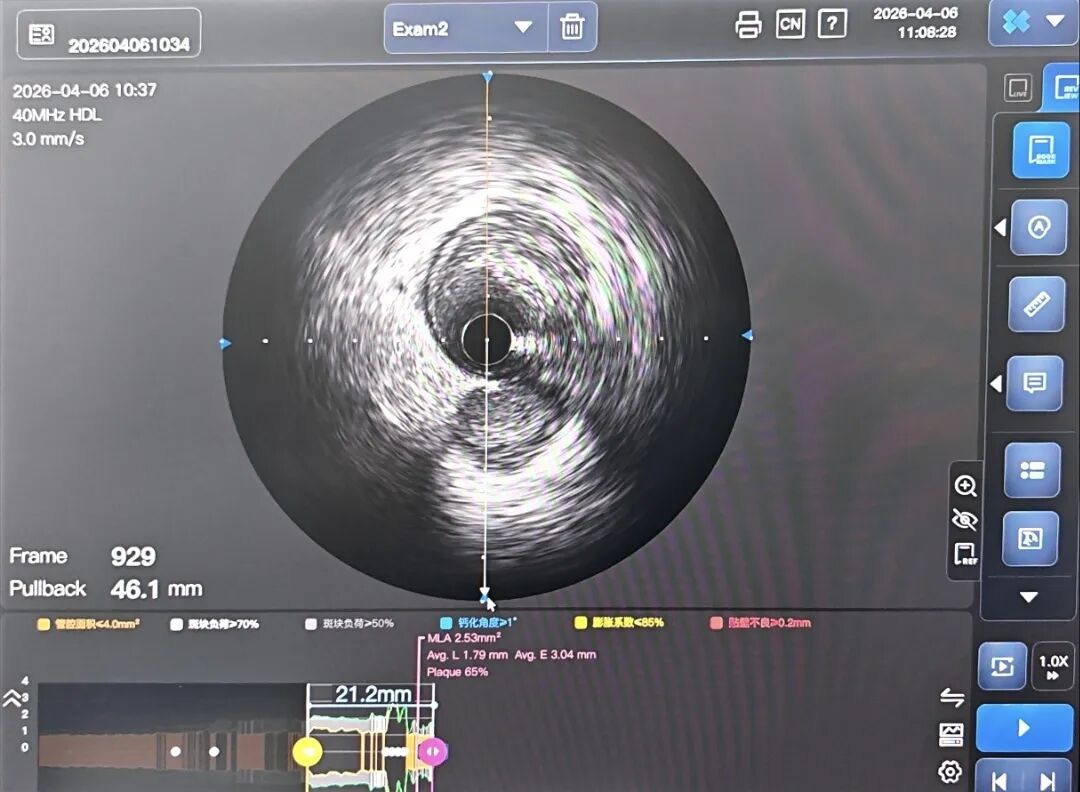

打开IVUS图像,可以看到导丝已经在超声导管下方,导丝伪影偏向7点钟,映射的探测器在4点左右。间隔支开口方向位置与造影图还有些差距(图22)。

造影导丝是什么如何用“化身导丝”的理念去理解和实现 IVUS-造影配准?_https://www.jmylbn.com_新闻资讯_第23张

前降支近段导丝从左往右走,也就是指向3点,我们把映射的探测器旋转到3点(图23)。现在可以看到IVUS屏幕上对角支开口与造影图非常接近,说明我们配准对齐了。